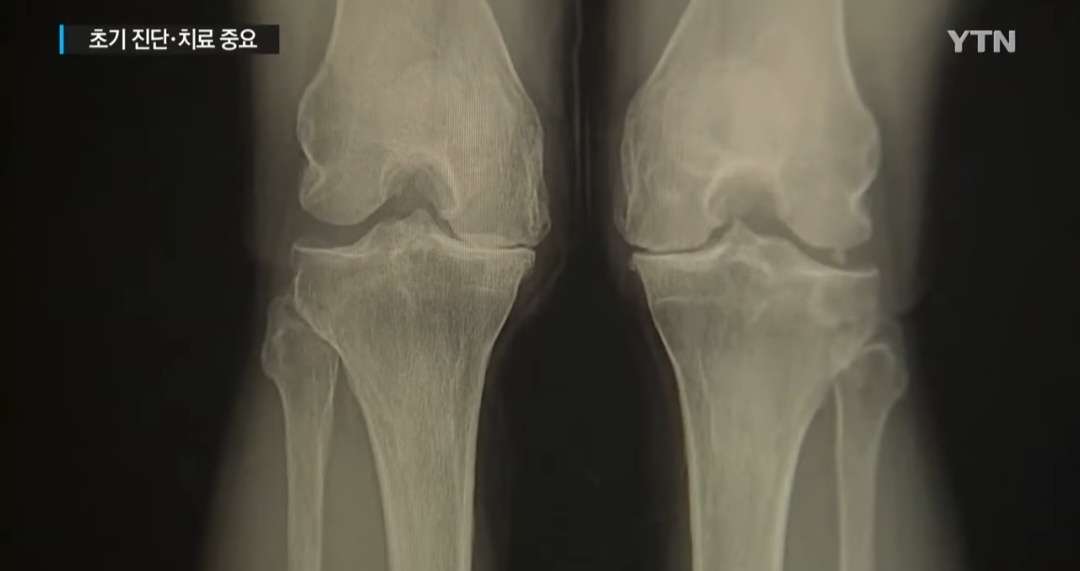

혼자서 하기보다는 두 사람이 같이 해보는 것이 좋습니다. 두 사람이 서로 마주보고 손을 마주 잡습니다. 진단을 받아볼 사람이 한쪽 무릎을 들고 다른 한쪽 다리로 중심축을 잡은 채 좌우 양쪽으로 움직여보는 것입니다. 한 다리를 진단해 본 다음에는 다리를 바꿔 다른 다리도 움직여봅니다. 이때 무릎에 불편한 느낌이 있거나 통증이 있다면, 초기 관절염을 의심해 볼 수 있습니다. 초기 관절염이 의심되면 병원에 가서 검사를 받아보는 것이 좋은데, 이 때 상황에 따라 권하는 것이 다를 수는 있으나, 꼭 고가의 MRI검사를 받지 않더라도, 엑스레이 검사만으로도 관절염의 진행상황을 알아볼 수 있으니, 의심이 될 때는 검사를 미리 받아 나의 상태를 전문가를 통해 정확하게 진단받는 것이 옳겠습니다. 통증이 심하거나 통증이 심하지 않더라도 무릎의 상태를 정확하게 파악하고자 때는 MRI검사를 받는 것이 정확합니다.

엑스레이 검사 MRI검사